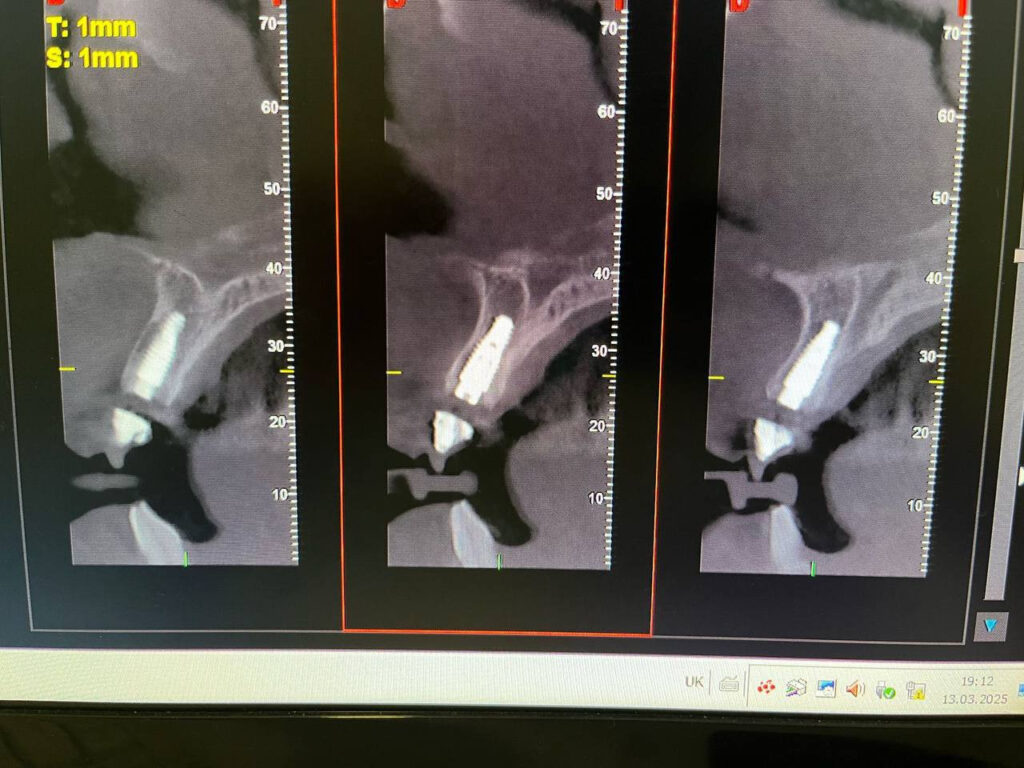

Конусно-лучевая компьютерная томография (КЛКТ) позволяет:

- Видеть кости, нервы, корни и синусы в 3D

- Точно планировать имплантацию

- Находить скрытые проблемы (кисты, воспаления и др.)